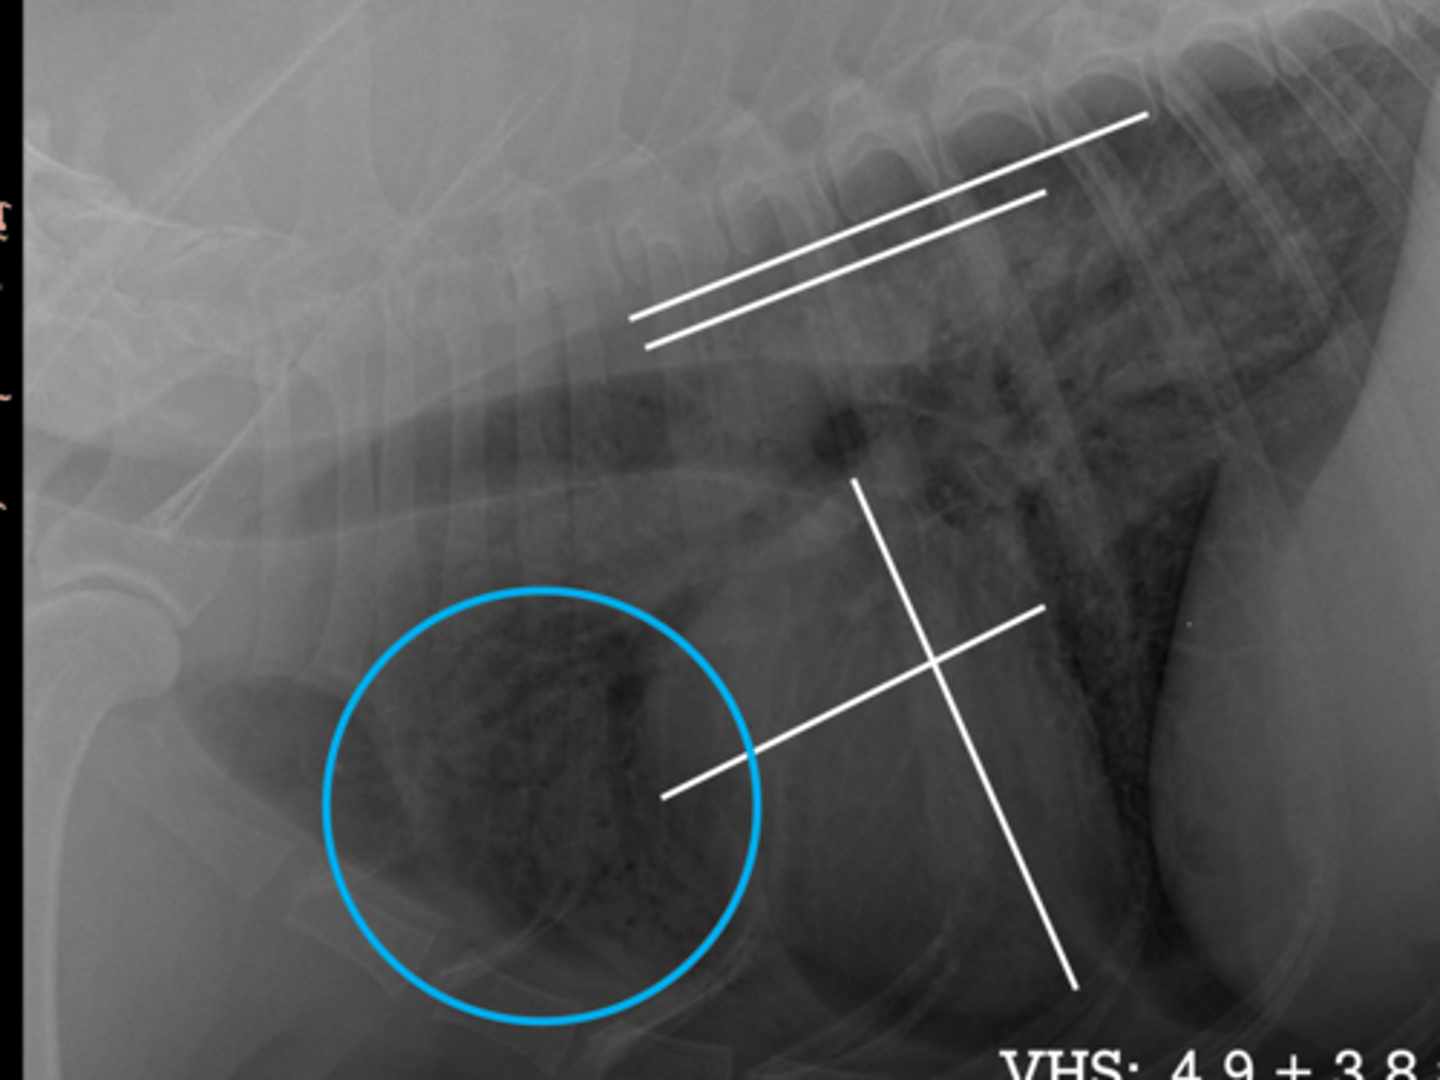

3.1 +4.2 =7.3

(Fel - 8)

Given the following radiograph do we have an enlarged heart?